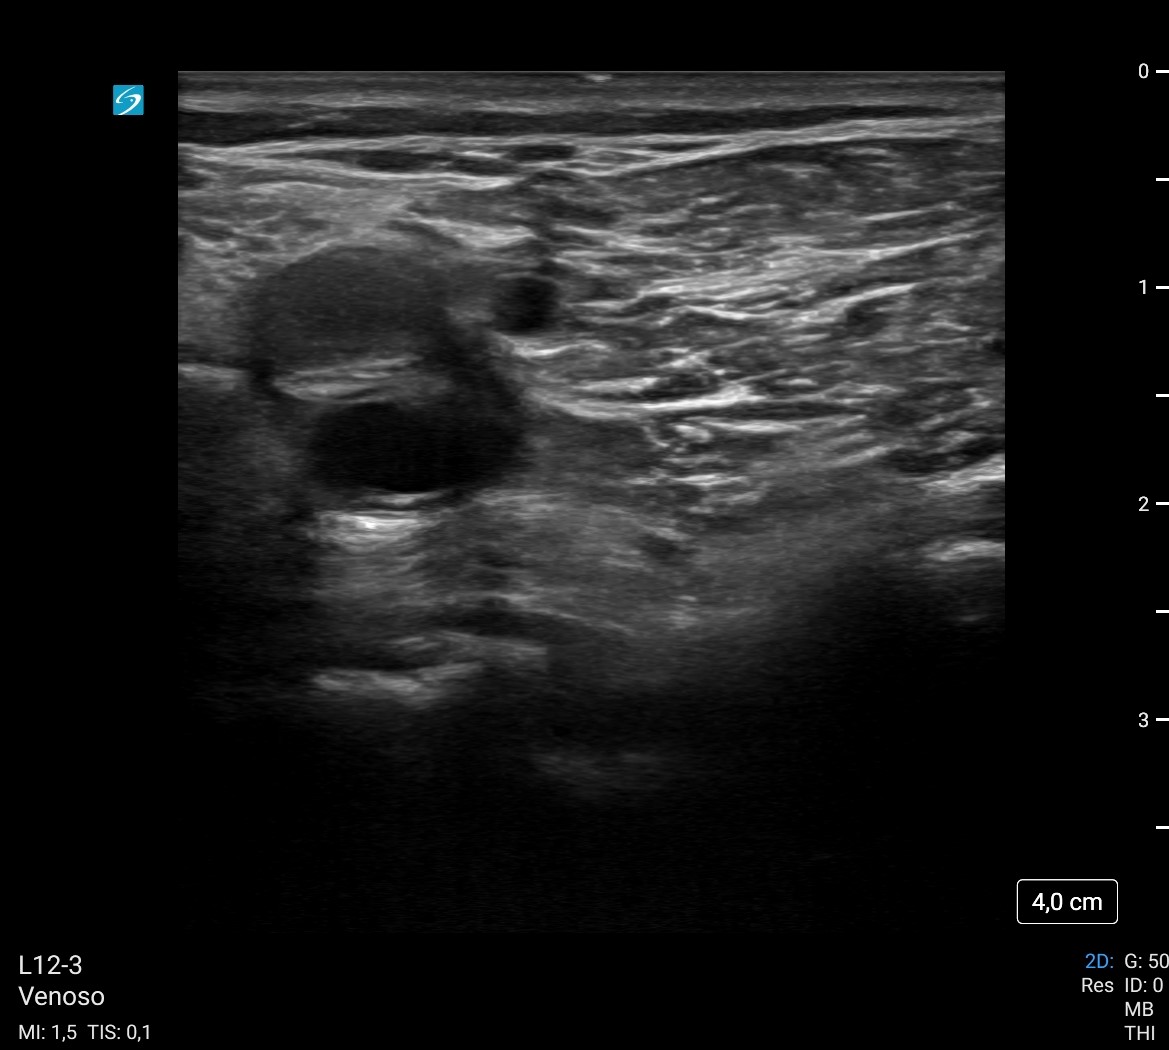

Asimismo, realizo ecografía clínica de sistema venoso profundo, observando una imagen hiperecogénica en vena poplítea, que no colapsa, todo ello compatible con TVP (a pesar de que el paciente tenía una exploración de EEII anodina).

El angioTC pulmonar solicitado confirmó nuestra sospecha: TEP bilateral, proximal y distal, con signos de hipertensión pulmonar y sobrecarga cardíaca derecha. Posteriormente, ingresó en Medicina Intensiva, donde se confirmaron la presencia de trombo intraventricular de 7-8 cm y la TVP poplítea. Se continuó con anticoagulación y el paciente evolucionó favorablemente.